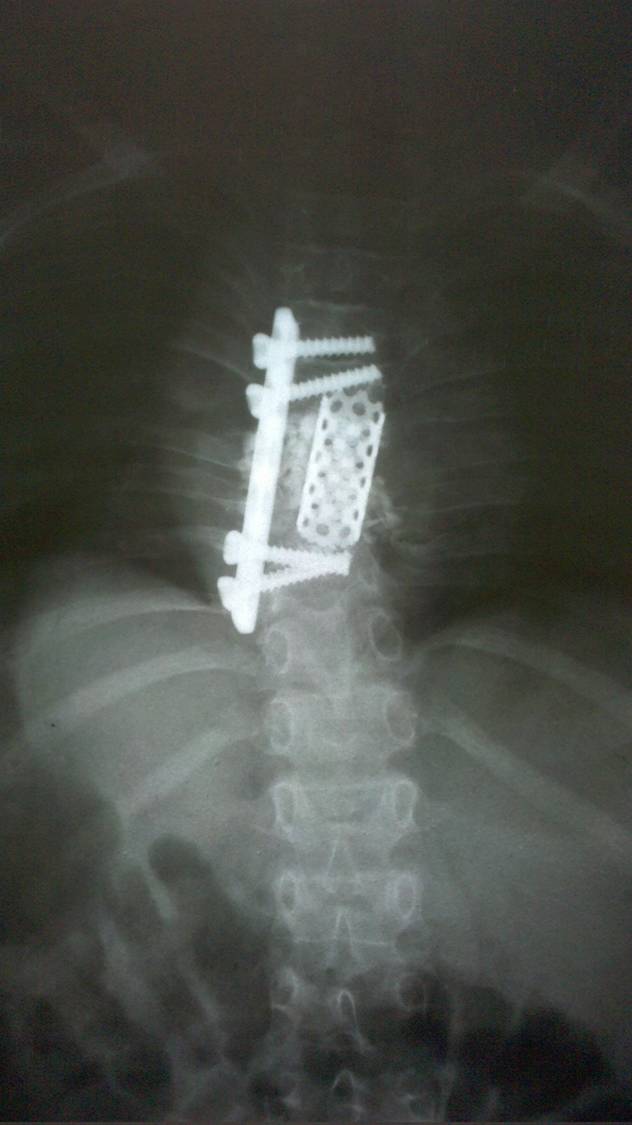

- Figura No 2a

- Figura No 2b

- Figura No 2c

- Figura No 2d

- Figura 2 Texto